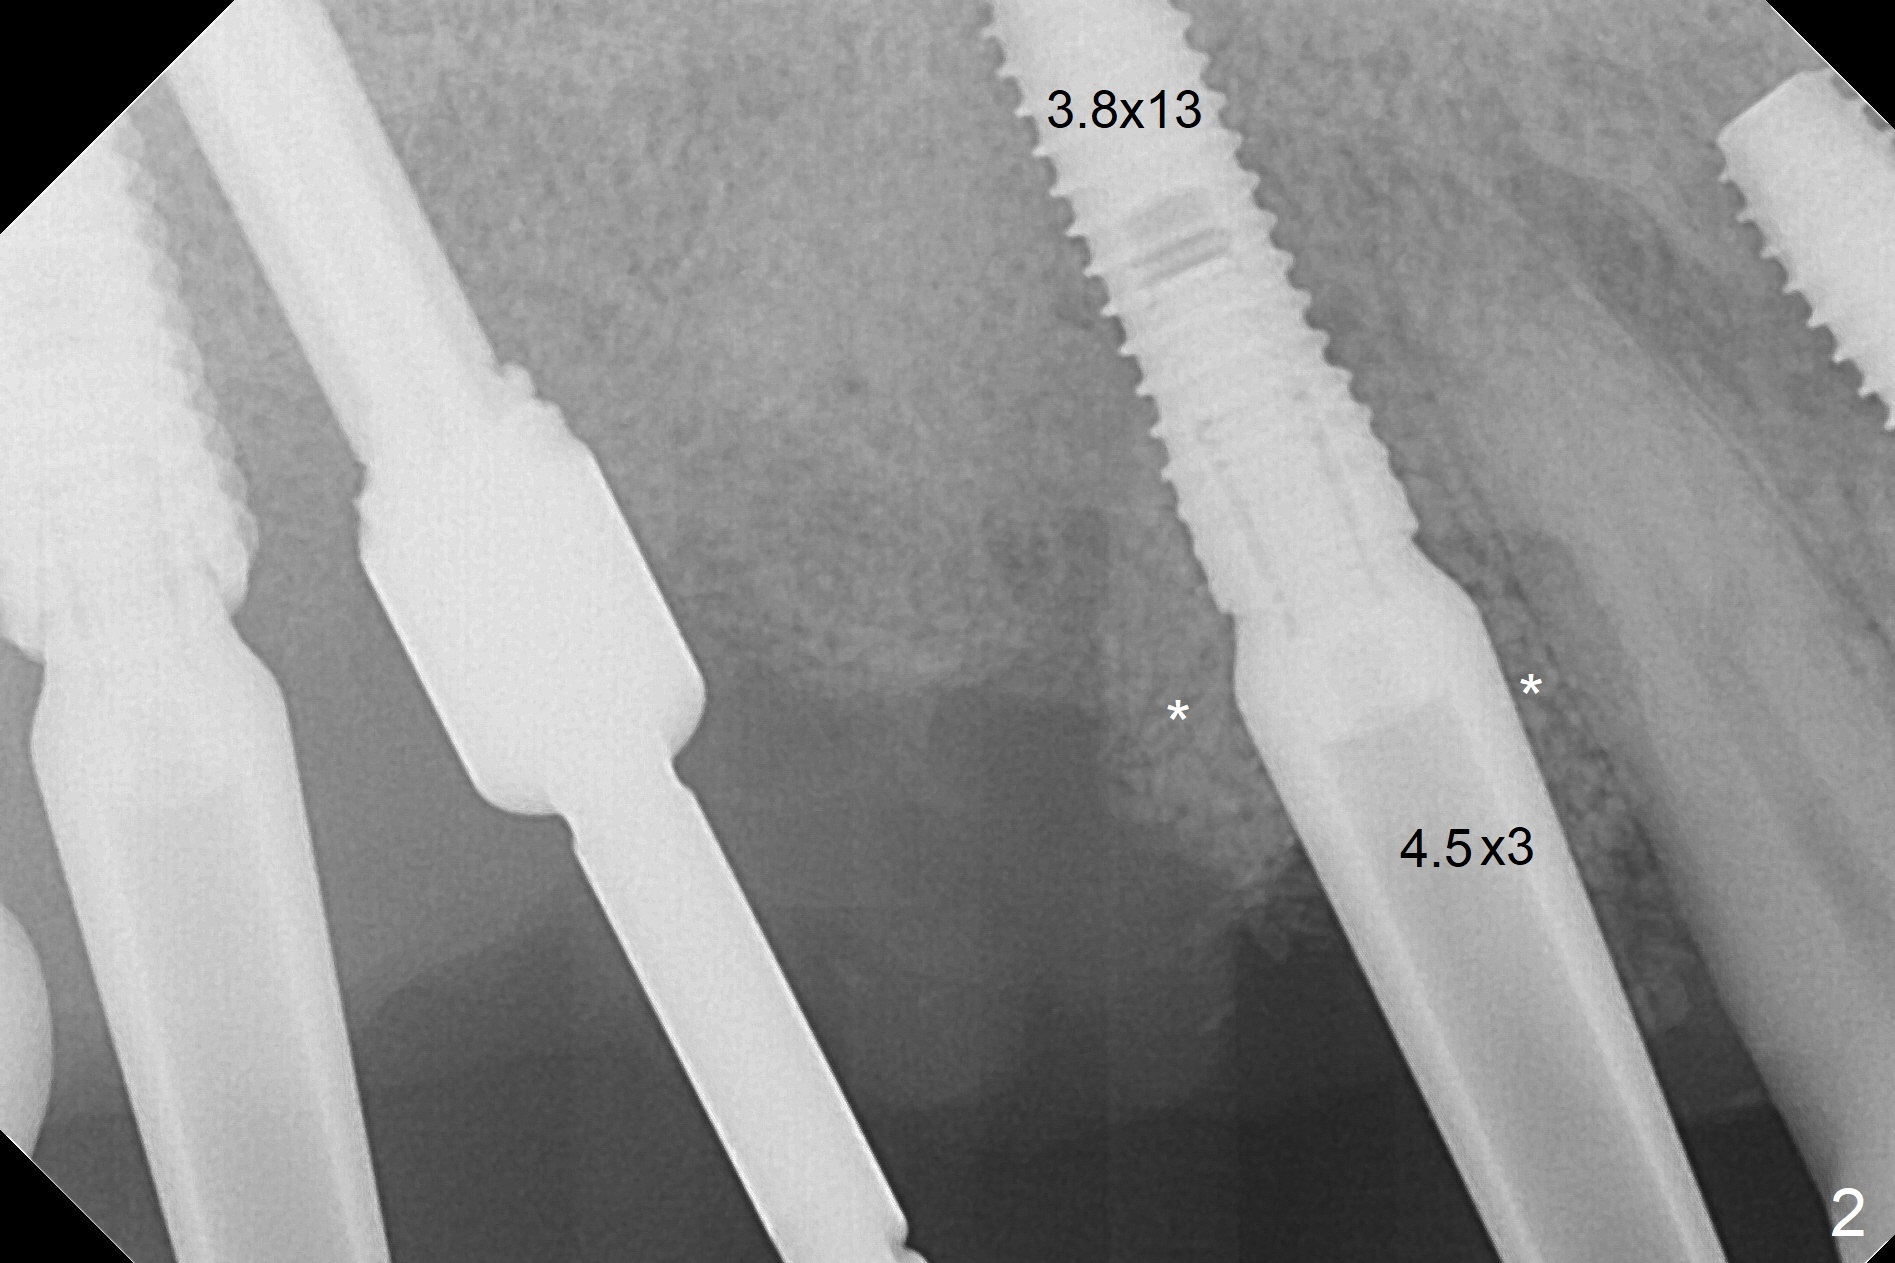

After extraction, the depths of initial osteotomy at #2, 3 and 5 are 13, 11.5 and 10 mm, respectively (Fig.1). Following adjustment of trajectory, a 3.8x13 mm UF implant is placed at #5 (Fig.2) with insertion of a 4.5x2 mm mill abutment as well as mineralized cortical/cancellous allograft (Vanilla, *). The mill abutment is chosen because the margin of a 5.5x7(5) mm cemented abutment is severely subgingival (Fig.4 at #3; ^ gingival margin). By the same token, a 4.5x3 mm mill abutment is placed at #2. In fact all of the 3 implants are placed 2-3 mm out of the bone (Fig.5). To prevent periimplantitis, abundant allograft is placed around the implants/abutments (Fig.2,4 *). Nearly 2 months postop, the mill abutment at #2 is adjusted for its height, while a 5.5x2.5 mm mill abutment is placed at #3 (Fig.6). To regain the buccal gingiva, the buccal margin of the provisional is shortened (Fig.6,7). Two weeks later, the gingival regrowth is not obvious (Fig.8 (nearly 3 months postop)). Local poor oral hygiene remains. A provisional FPD is fabricated. If his occlusion is normal for another 2 weeks, impression will be taken for upper (or UL) permanent restoration.